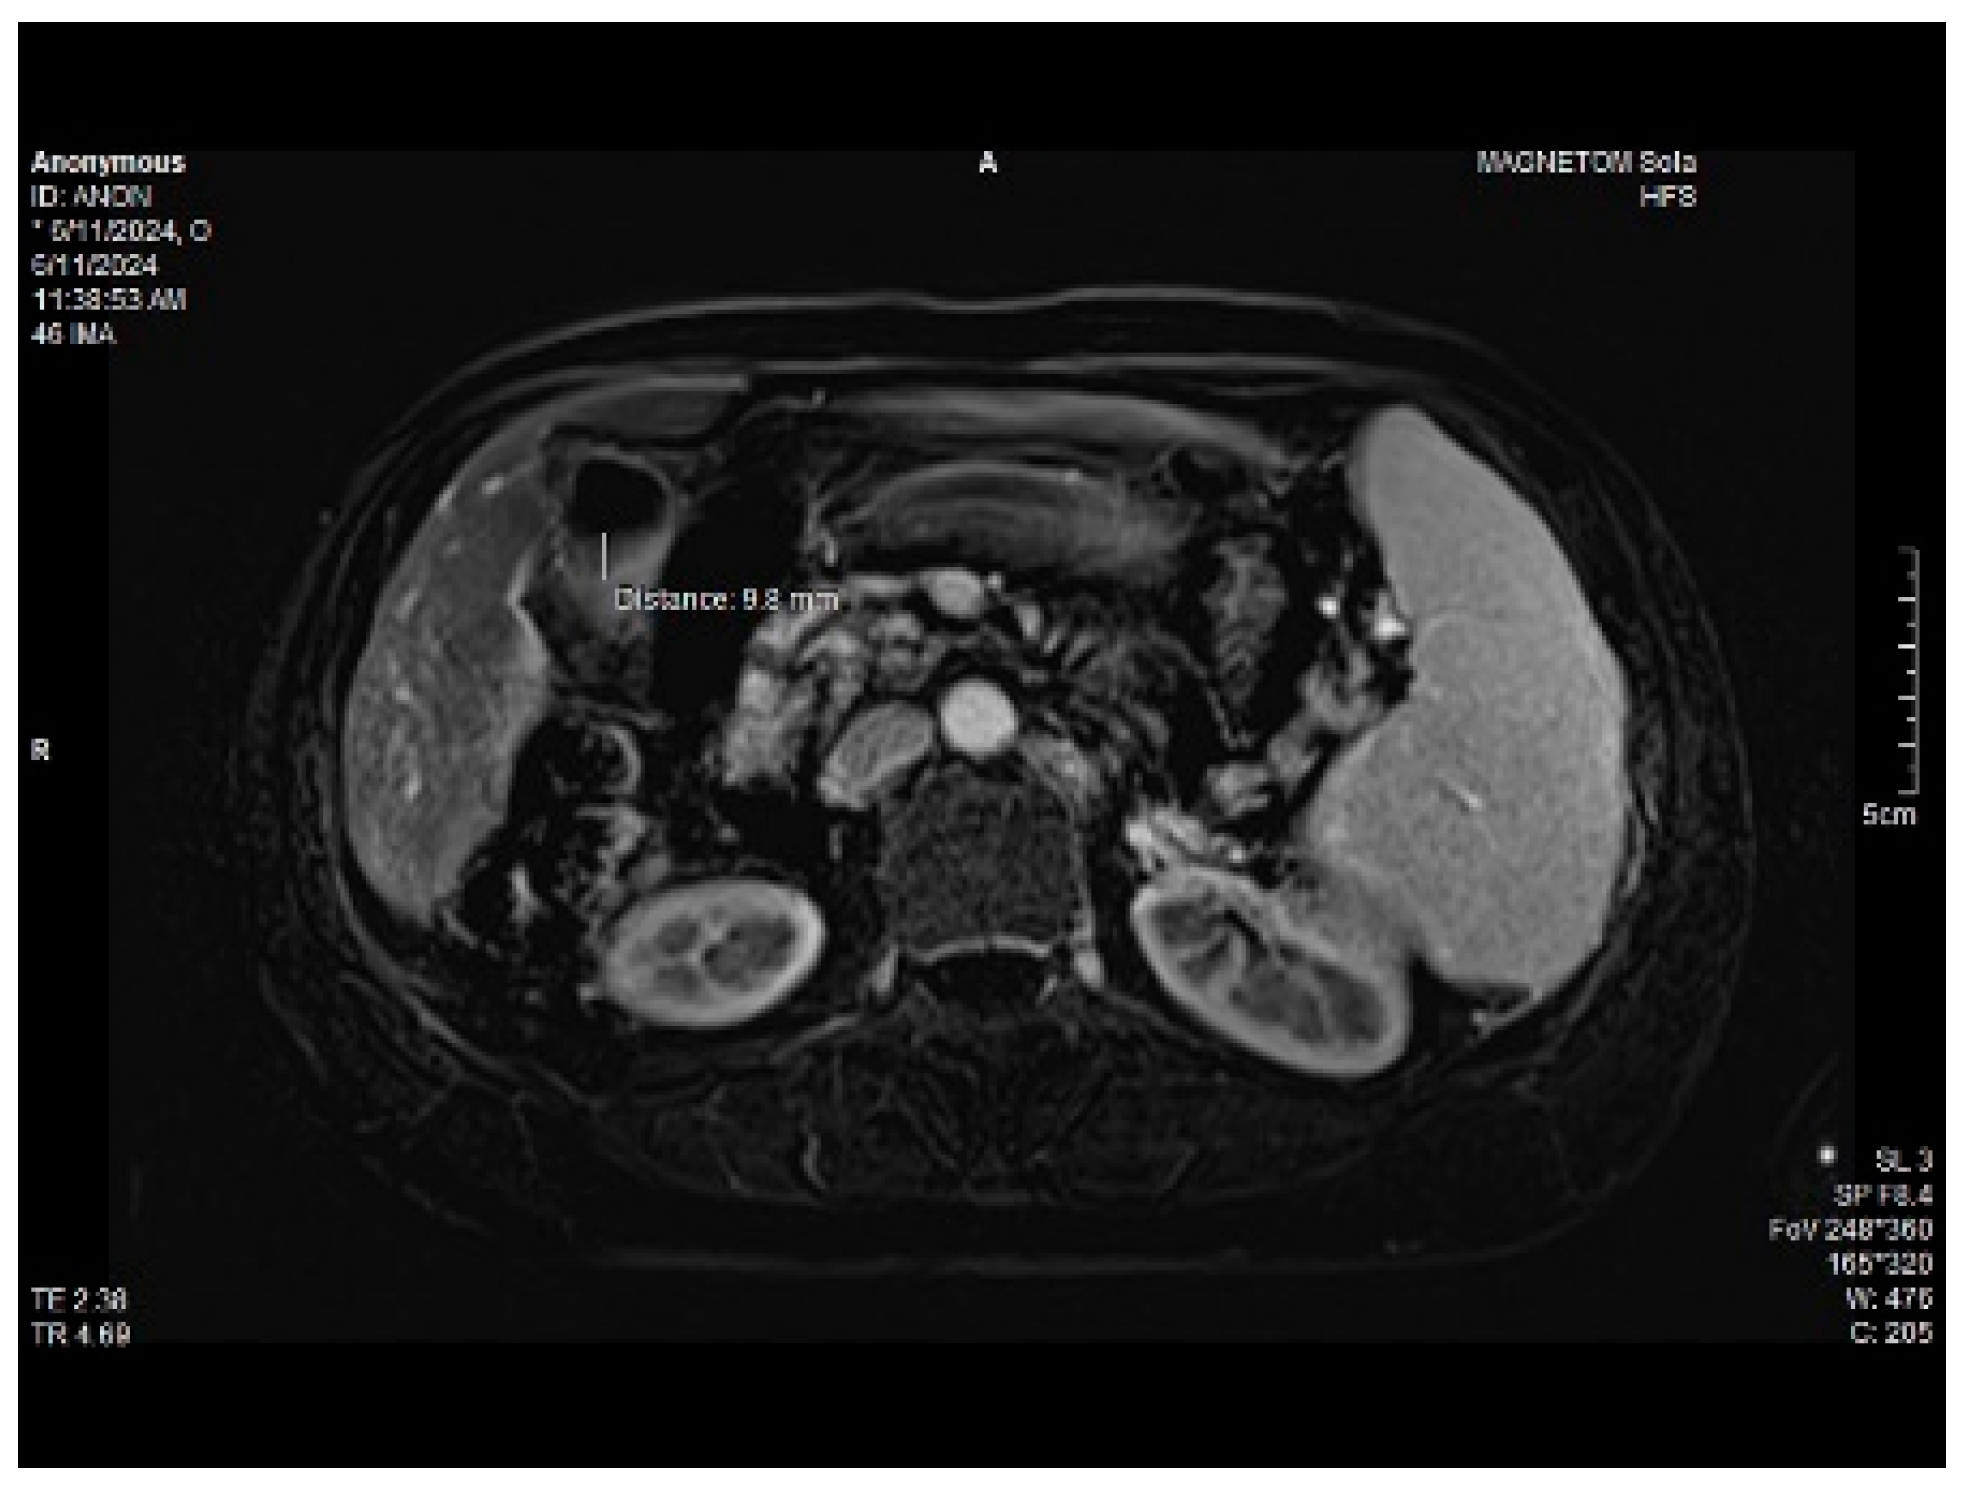

A 65-year-old female was admitted to the outpatient department in late 2023, complaining about the insidious onset of fatigue, slight abdominal pain and weight gain. The patient’s medical history highlighted a rectal adenocarcinoma (T2N1M0) diagnosed in 2014, treated by surgery, chemotherapy (4× FUFOL) and radiotherapy. The histology of the adenocarcinoma is presented below, in Figure 1.

Figure 1. Adenocarcinoma showing moderately differentiated glands filled with necrotic debris. HE stain, 400× magnification (left); hyperplastic polyp with “sawtooth” appearance, mild nuclear enlargement and no horizontal crypts, HE stain, 200× magnification (right).